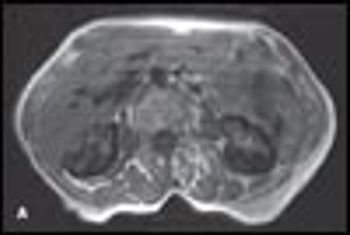

MRI scans of the kidneys of an 83-year-old woman with history of myelodysplastic syndrome are shown. Normal MRI scans are shown for comparison. The patient had intermittent episodes of dark-colored urine for years. Findings from repeated cystoscopies were normal.